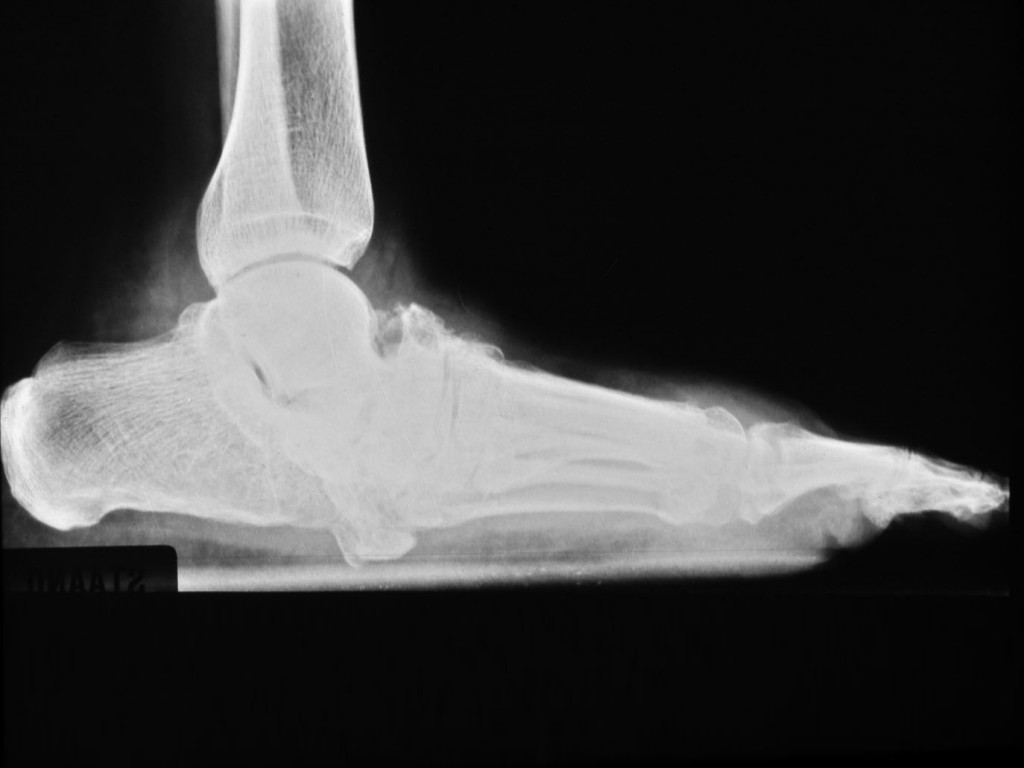

trauma, en aan de tenen en voetzolen door druk

of knellende schoenen. Het voetgewelf zakt in waardoor er een bolle voet ontstaat

met nieuwe drukpunten midden onder de voet. De

ingezakte voet

wordt vaak een

Charcot voet of

rockerbottom

voet genoemd. De tenen gaan in een dwangstand staan en krijgen

nieuwe drukpunten aan de bovenkant en aan de onderkant. De

wondjes

en

drukulcera zijn vaak bedekt met een dikke laag

eelt (

callus), gaan dieper dan aan de buitenkant zichtbaar

is en kunnen infecteren en overgaan in een

osteomyelitis.

Vaak moeten tenen en vingers worden geamputeerd vanwege infectie en osteomyelitis.

De botten in de distale kootjes zijn vaak aangetast en tonen

botresorbtie,

door infectie en/of door de innervatiestoornis. Er ontstaan

plantaire

ulcera en

drukulcera, vaak is amputatie

of resectie van een hele straal of voorvoet nodig. De neuropathische voet bij

lepra lijkt op die bij diabetes. Het verschil is dat de neuropathie bij lepra

erger is en dat bij diabetes er vaak ook arterieel vaatlijden bij is en een

verhoogde kans op infectie.

| normaal

voetgewelf |

ingezakt